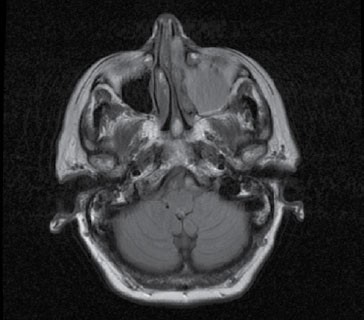

En nasofibroscopia se observa tumoración en fosa nasal izquierda, decidiéndose ampliar estudio con TAC con neuronavegador en el que se describe: tumoración en fosa nasal izquierda, de contornos imprecisos que ocupa prácticamente la totalidad del vestíbulo nasal, oblitera el meato medio y rechaza el tabique nasal. Condiciona ocupación secundaria, probablemente por obstrucción el flujo de drenaje, de los senos maxilar, frontal y celdillas etmoidales izquierdas, con remodelación de las paredes óseas del seno maxilar izquierdo.

|

| Figura. Corte horizontal TAC |

Ante este hallazgo se realiza biopsia con resultado de neuroblastoma olfatorio.